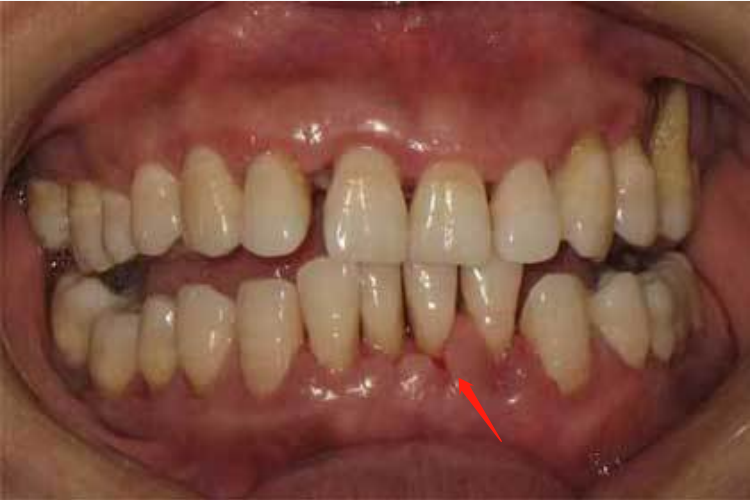

牙周炎:牙周炎症状与牙龈炎类似,除此之外还会有牙周袋形成。

牙周炎:常见病因包括牙石、食物嵌塞、不良修复体、牙排列拥挤等,全身因素仍不明确,可能与营养代谢障碍、内分泌紊乱等有关。